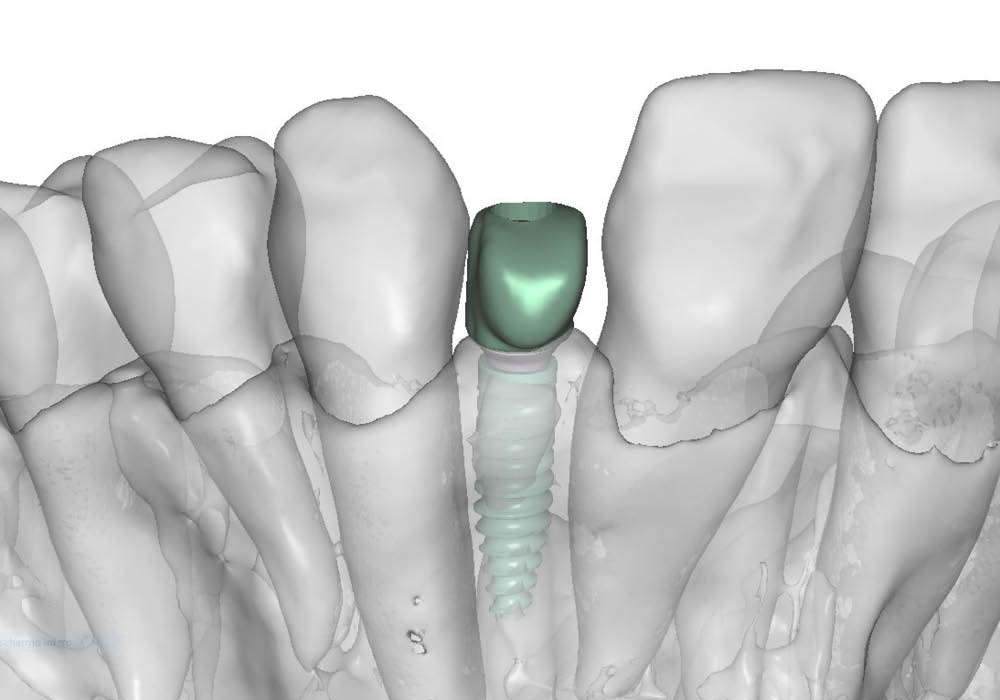

3. Pianificazione chirurgica

La pianificazione chirurgica ha previsto un’analisi tridimensionale dettagliata del sito implantare, valutato sia da angolazioni multiple sia in visione frontale diretta.

L’obiettivo era quello di definire con precisione posizione, profondità e inclinazione dell’impianto, tenendo conto della vicinanza delle radici adiacenti e della necessità di preservare un adeguato spessore vestibolare.

Questa fase ha permesso di anticipare eventuali criticità e assicurare l’inserzione corretta all’interno dei limiti anatomici disponibili.

5. Costruzione del tappo di guarigione in PEEK

Su misura per la paziente, è stato realizzato un tappo di guarigione anatomico in PEEK, progettato per guidare correttamente la guarigione dei tessuti molli e mantenere il profilo di emergenza ideale in funzione del futuro restauro.